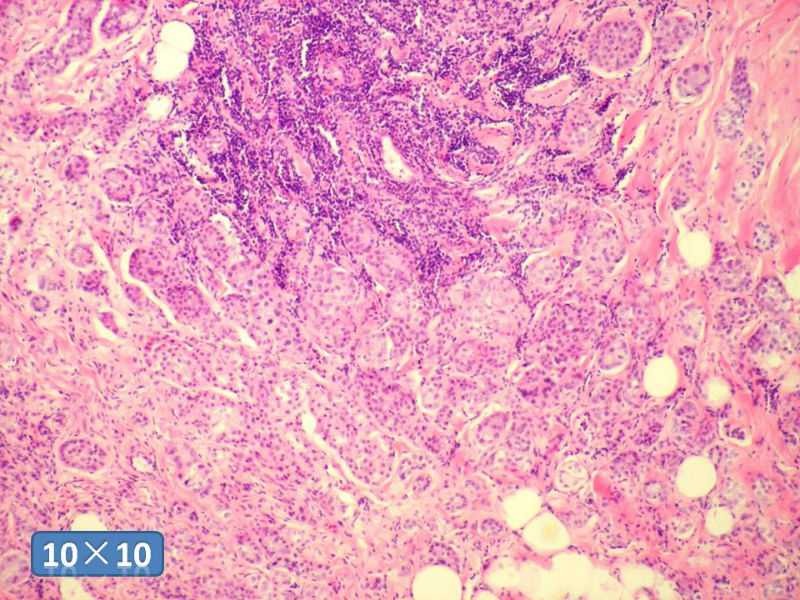

女性,50岁,乳腺肿物,冰冻切片(图1-25)

HE

IDC